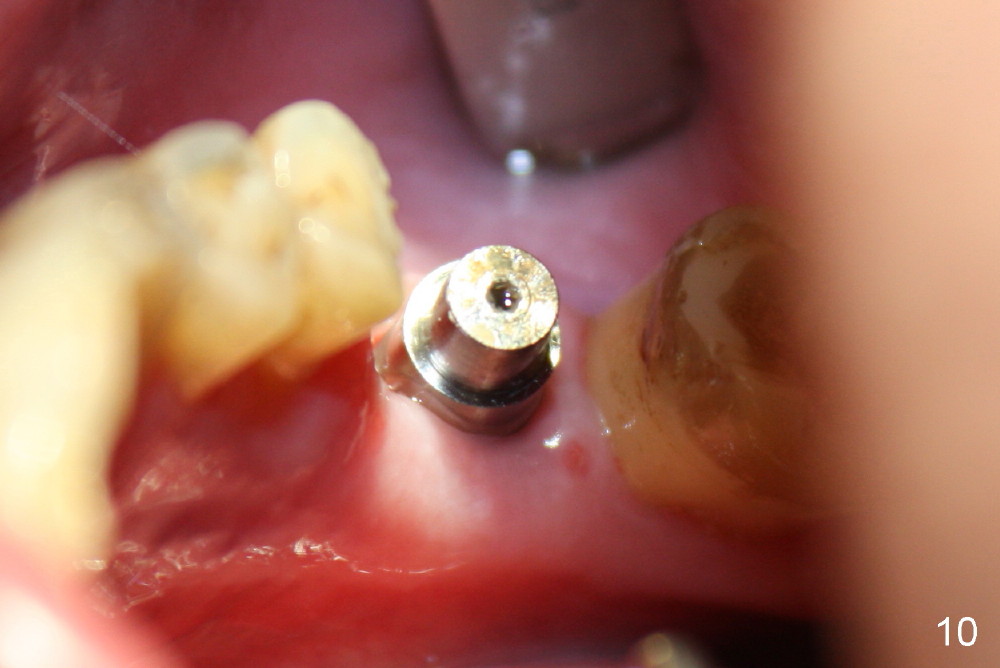

When the perio dressing is removed in office 24 days postop (Fig.9), the rough surface of the implant (R) is exposed buccally. Normally the smooth surface should contact the gingiva (S). Lingually implant/gingiva position is within normal limit (Fig.10). The patient returns for restoration 4 months postop (Fig.11,12). There is bone formation in the mesial socket and new bone appears to have grown toward the implant (Fig.11 <). A straight abutment appears to be in the middle of the edentulous space (Fig.12 A). But it is difficult to seat the crown. Three months post cementation, the patient complains of food impaction mesially (Fig.10 ^), although bone density continues to increase in the mesial socket and there is no mesial coronal thread exposure (*). Retrospectively the implant should be tried to be placed in the septum as much as possible to have a favorable restorative axis (Fig.14). The crown is re-fabricated with larger mesial contact area. It is temporarily cemented because of slightly loose distal contact (Fig.15). A few days later, the patient requests permanent cementation, because although the distal contact is loose, it is easy to remove food. Mesial food impaction is less likely, but it is more difficult to be removed.